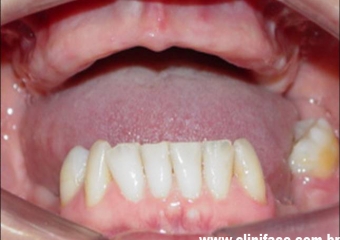

Prótese fixa em porcelana instalada sobre os implantes

Sorriso final do caso terminado em julho de 2009